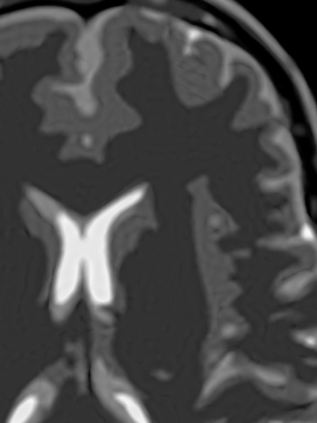

Implicit neural representations (INRs) have emerged as a powerful tool for solving inverse problems in computer vision and computational imaging. INRs represent images as continuous domain functions realized by a neural network taking spatial coordinates as inputs. However, unlike traditional pixel representations, little is known about the sample complexity of estimating images using INRs in the context of linear inverse problems. Towards this end, we study the sampling requirements for recovery of a continuous domain image from its low-pass Fourier coefficients by fitting a single hidden-layer INR with ReLU activation and a Fourier features layer using a generalized form of weight decay regularization. Our key insight is to relate minimizers of this non-convex parameter space optimization problem to minimizers of a convex penalty defined over an infinite-dimensional space of measures. We identify a sufficient number of samples for which an image realized by a width-1 INR is exactly recoverable by solving the INR training problem, and give a conjecture for the general width-$W$ case. To validate our theory, we empirically assess the probability of achieving exact recovery of images realized by low-width single hidden-layer INRs, and illustrate the performance of INR on super-resolution recovery of more realistic continuous domain phantom images.